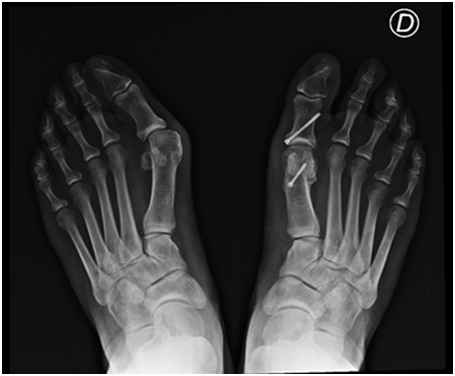

If the Hallux Abductus Angle is more than 30 degrees or the deformity is classified at least as moderate (grade 3) using the Manchester Scale.4 an Akin phalangeal osteotomy.2 is always added and fixed with a cannulated double threaded 2.5 mm screw across the osteotomy line (Figure 3 & 4).

Figure 3 Postoperative X-rays 3 weeks after surgery.